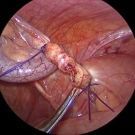

A 73-year-old man with a history of hyperlipidemia, hypertension, diabetes, and degenerative joint disease who had undergone left knee total replacement approximately 3½ years ago presented with a 1-day...

12/05/2019